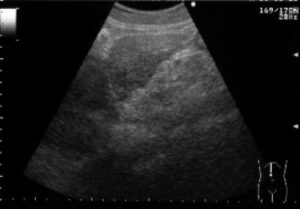

最近は、ご自分で妊娠反応を確かめてみえるかたも多いですが、妊娠の確定診断には超音波検査が必要です。妊娠反応の感度がとてもよくなったため、妊娠反応がでても超音波で赤ちゃんをいれている袋が見えない時期というのが数日から1週間程度あります。妊娠週数の計算法は、生理がはじまって14日目に排卵がおこっていることを前提としているため、超音波で赤ちゃんが見えない場合には、「実際に排卵したのは14日目よりも遅く、病院にくるのがはやかったのでみえない」「妊娠は成立したが、何らかの理由で正常に進行していない」「異所性(子宮外妊娠)」の3つの場合があります。

妊娠週数は最後の生理が始まった日から数えて280日目を分娩予定日とし、週数で数えます。28日周期で生理が合っている方だと、4週0日が次の生理の予定の日となります。 おおむね5-6週で、赤ちゃんのはいっている袋(胎嚢)がみえてきます。赤ちゃんの心拍がみえるようになるのが7週前後です。8週から11週にかけての赤ちゃんの大きさを計測して、生理から計算した分娩予定日とのずれが大きければ予定日を修正します。そしてその後は母子手帳をお渡しして、いわゆる妊婦健診を開始します。